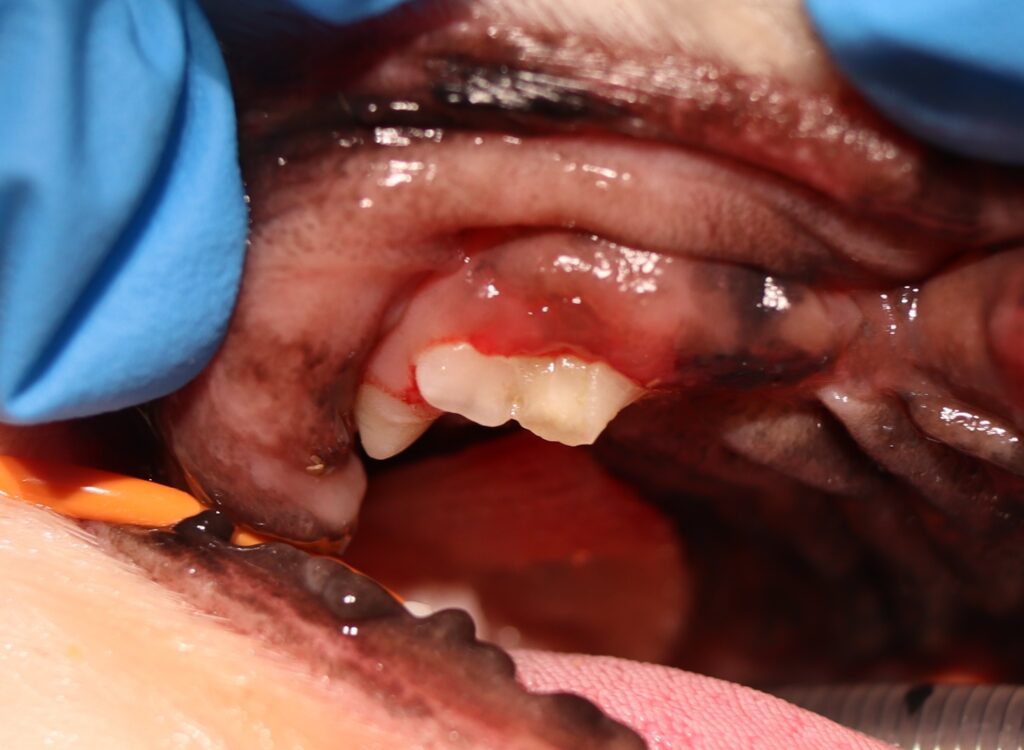

🦷 症例紹介:右上第四前臼歯の破折

今回は、犬で比較的多い上第四前臼歯の破折について解説します。

幸い、この症例では神経(歯髄)は露出していない「非露髄破折」でした。

歯の内部の神経が露出していない状態を「非露髄破折」といいます。